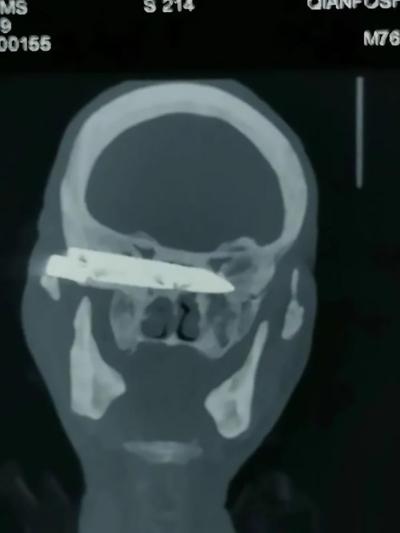

Following a number of CT scans and X-rays, medics reportedly found that the blade was placed at the base of the patient’s skull, lodged against his eye socket and pressing against his optic nerve.